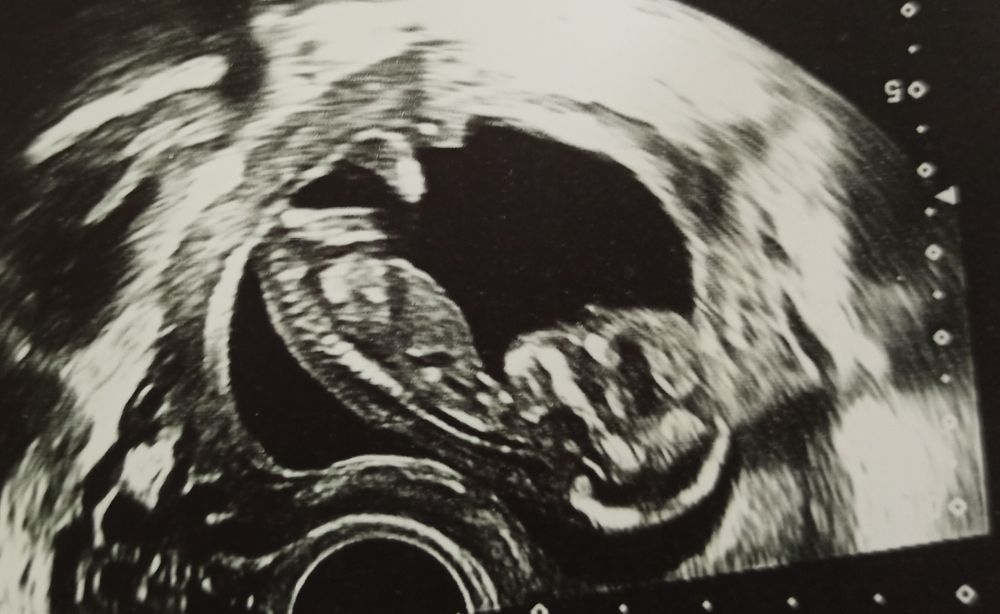

12 недель. Первый скрининг